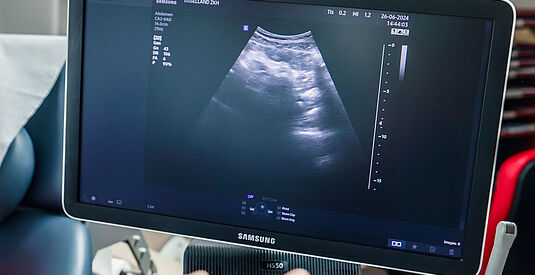

Complicaties tijdens de zwangerschap

Er zijn een aantal complicaties die kunnen ontstaan tijdens de zwangerschap. Bekijk de filmpjes Hoe kom ik in het geboortecentrum, Spoedconsult tijdens de zwangerschap en Opname tijdens de zwangerschap.